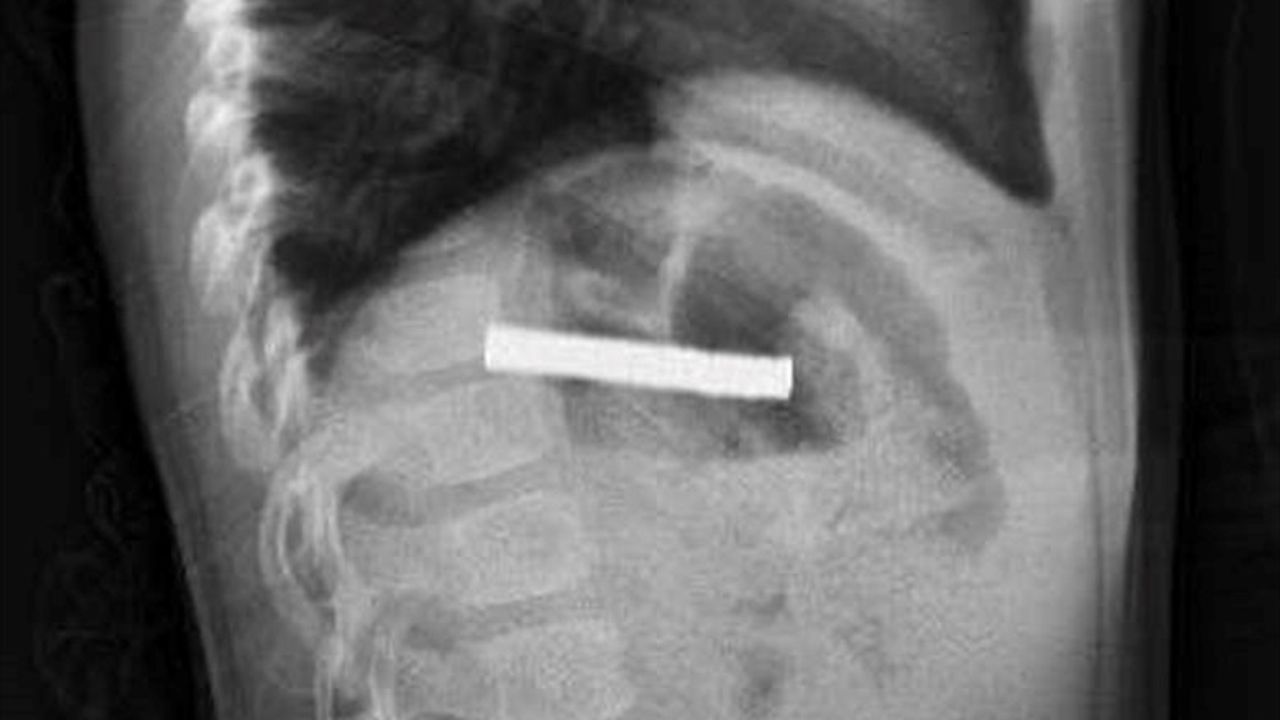

Erzurum'da evde oyun oynarken bulduğu 19 mıknatısı yutan 3 yaşındaki çocuk, rahatsızlanması üzerine ambulansla Erzurum Şehir Hastanesi'ne kaldırıldı. Yapılan tetkiklerin ardından hasta, acil durum nedeniyle ambulans helikopter ile Fırat Üniversitesi (FÜ) Hastanesi'ne sevk edildi.

FÜ Çocuk Gastroenteroloji Hepatoloji ve Beslenme Bilim Dalı Başkanı Prof. Dr. Yaşar Doğan ve ekibinin tetkiklerinde mıknatısların birbirine yapışarak çocuğun yemek borusunu tıkadığı tespit edildi. Müdahale sırasında mıknatıslar yemek borusundan mideye alınarak, mideden özel bir file ile çıkarıldı. İşlem başarılı geçti.

Elazığ'da 3 yaşındaki çocuğun yuttuğu ve yemek borusunu tıkayan 19 mıknatıs, Fırat Üniversitesi Hastanesi'nde yapılan başarılı bir operasyonla çıkarıldı.